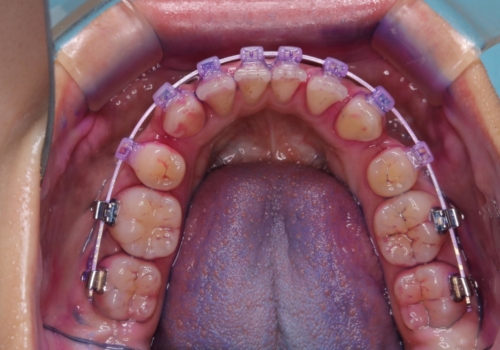

ワイヤー矯正中のクリーニング

- ワイヤー矯正中に、磨ききれないところがあるのと、口臭が気になるとのことでした。

そのためPMTC30分コースを行いました。

ワイヤー矯正中は、装置の周りに汚れが付きやすく虫歯や歯周病のリスクが高まります。そのため、ワイヤー調整の診察の際、一緒にクリーニングを行うことで、虫歯・歯周病・口臭予防になります。歯ブラシだけでは取り除くことが難しい細かい部分などに、専門的な機械や機材を使用して定期的なケアを行うことをおすすめしています。